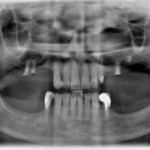

Riabilitazione con approccio multidisciplinare Caso clinico

La riabilitazione di pazienti edentuli con protesi mobile si associa solitamente a diverse limitazioni. Le soluzioni supportate da impianti stanno sempre più confermando la...